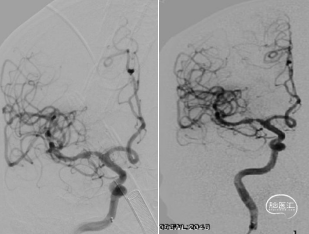

右侧大脑中动脉闭塞。

左侧颈内动脉显影正常,未见向右代偿。

右侧椎动脉优势,未见向前代偿。

考虑到血栓抽吸导管系统(ACE 68)头端抗抽瘪和优异通过性的特点,使用ACE 68快速高到位,微导丝携带微导管Rebar18 超选至R-M2段,造影证实在真腔。

造影考虑ICAS病变,通过微导管Rebar18输送5*30mm Reco取栓支架,施行SWIM技术。

SWIM技术取栓过程:ACE 68同轴到位M1起始段,回撤Reco取栓支架同时持续ACE 68向前跟进,减少血栓逃逸的同时将血栓拉进ACE 68并撤出体外。

一次取栓实现血管再通,复查造影提示R-M1局限性狭窄,观察20分钟复查造影R-M1局限性狭窄无明显回缩,前向血流III级,因前向血流速度正常,故原位狭窄暂不同期处理,待病情稳定后择期处理。